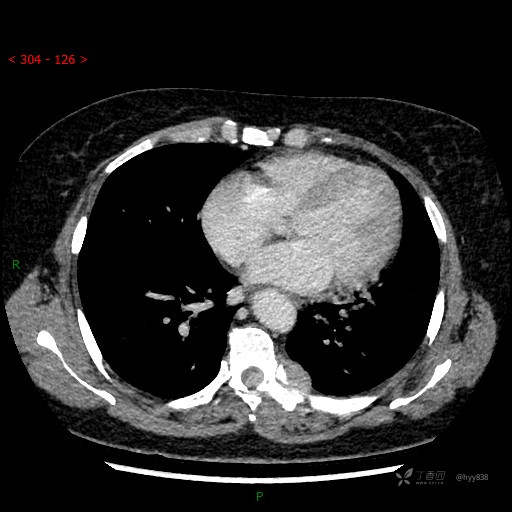

增强